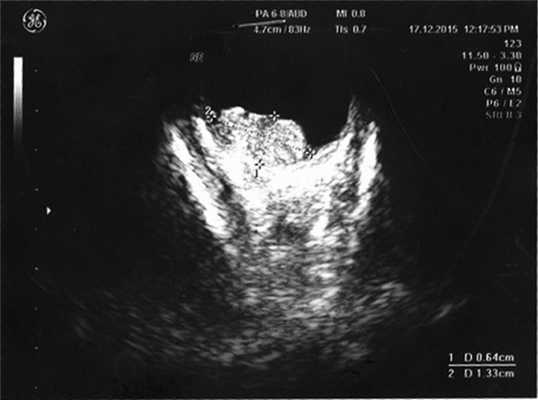

Диагностика внутриглазной медуллоэпителиомы является трудной задачей. Сочетание таких клинических признаков как плотная ретролентальная мембрана, подвывих хрусталика, вторичная гипертензия позволяют заподозрить внутриглазную опухоль. Выявление при ультразвуковом исследовании гетерогенной ткани, включающей анэхогенные зоны, подтверждает наличие медуллоэпителиомы.

Согласно данным ультразвукового исследования, у заднего полюса выявлены плюс-ткань гетерогенной эхоструктуры с единичными кальцинатами, размером 6,4×13,3 мм, вторичная отслойка сетчатки (рис. 2). Учитывая локализацию опухоли (солитарный опухолевый узел, полностью перекрывающий ДЗН), отсутствие шансов на зрение, размеры образования и высокий риск экстрабульбарного распространения опухоли, выполнена энуклеация левого глаза с пластикой культи. После получения патогистологического заключения (злокачественная медуллоэпителиома) ребенок направлен на консультацию к детскому онкологу с целью возможного выявления новообразования в головном мозге. По данным магнитно-резонансной томографии, опухолевых очагов в ЦНС не выявлено, однако в связи с прорастанием опухоли за laminacribrosa пациенту назначен курс лучевой и химиотерапии (циклофосфан, вепезид, карбоплатин).

Рис. 2. Результат эхографии левого глаза у ребенка с подозрением на монокулярную форму ретинобластомы.